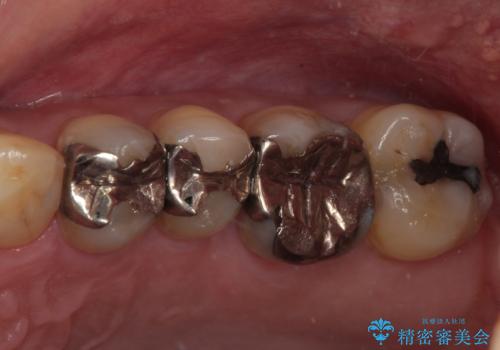

銀歯をセラミックにしたい オールセラミッククラウン

担当医 有澤哲郎